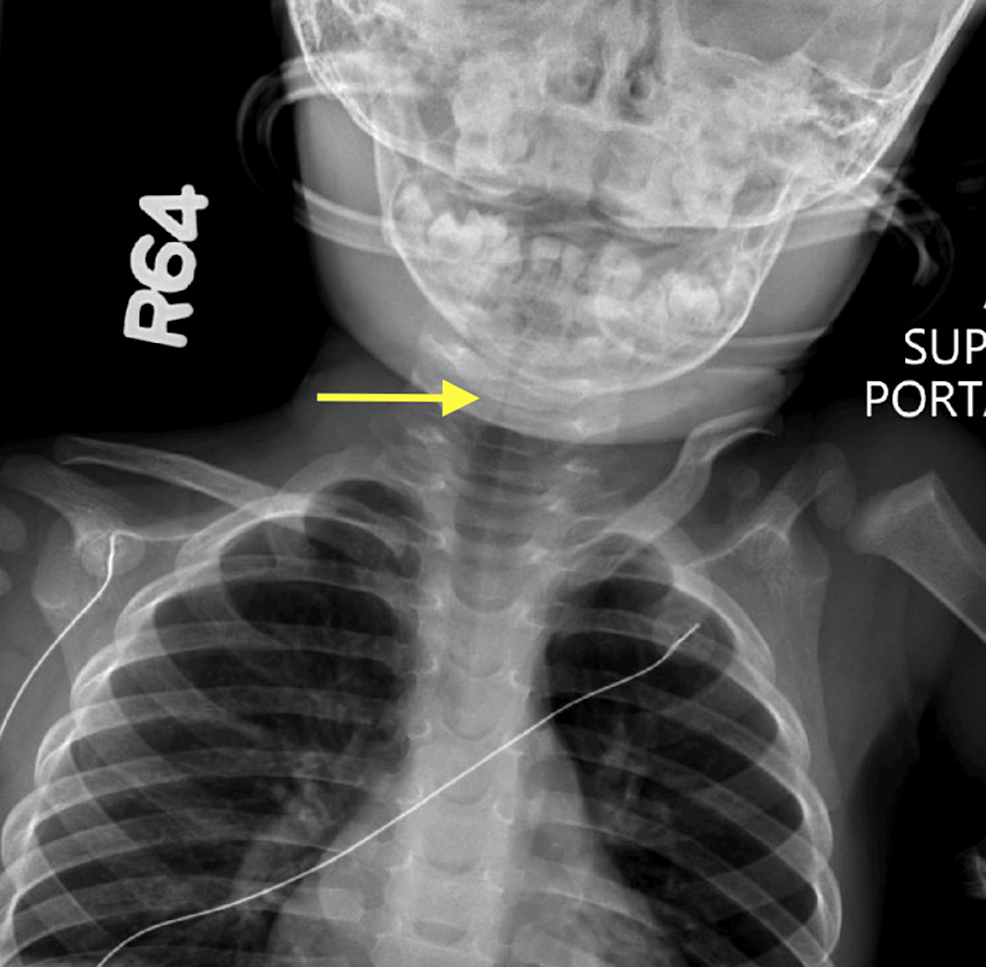

Cureus Recurrent Subglottic Stenosis in a 16MonthOld Male in the Is Subglottic Stenosis A Respiratory Disease   idiopathic subglottic stenosis (isgs) is a fibrotic disease of unclear etiology that produces obstruction of the central airway.   identify subglottic stenosis risk factors in patients, including a history of intubation, recurrent respiratory.   learn about idiopathic subglottic stenosis, including symptoms, causes, and treatments.   in acquired subglottic stenosis, there is progressively worsening shortness of breath, which could become. Is Subglottic Stenosis A Respiratory Disease.